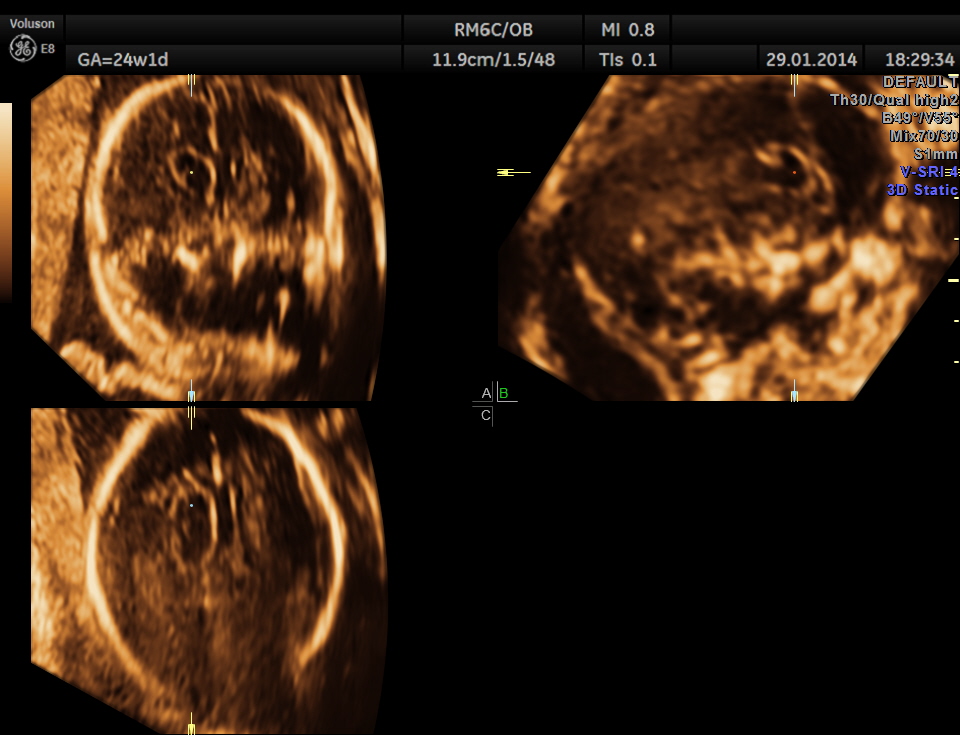

The following images were obtained. Unilateral choroid plexus cyst was seen .